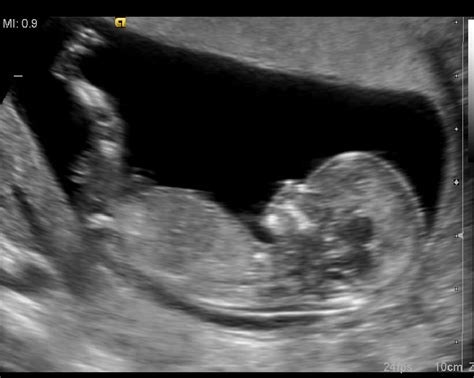

Rizična nosečnost je stanje, pri katerem obstaja povečana verjetnost za zaplete med nosečnostjo, porodom ali po porodu, ki lahko ogrozijo zdravje ali življenje matere ali otroka. Diagnoza rizične nosečnosti temelji na celovitem pregledu nosečnice, s katerim zdravnik ugotovi morebitna bolezenska stanja in dejavnike tveganja. Ti dejavniki tveganja so lahko prisotni že pred zanositvijo ali pa se razvijejo med samo nosečnostjo.

Prvi pregled v nosečnosti pri ginekologu